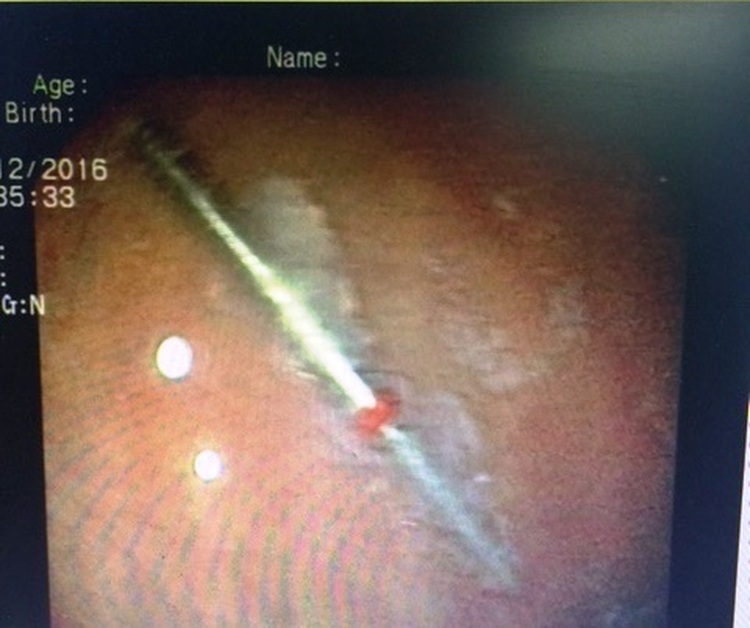

Doctors at the An Binh Hospital, located in District 5, on Thursday removed a three centimeter long pointed dental drill bit, from D.T.M.H., a 56-year-old resident in the southern Vietnamese city.

The initial diagnosis confirmed that the burr was stuck in her stomach, causing scratches and bleeding in the antrum.

Doctors at the infirmary chose to extract the object using an endoscopic technique.